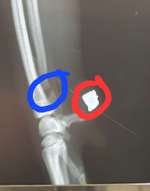

Hallo, ich habe gerade meine Hündin erwischt, wie sie auf einer Verpackung rum biss,jetzt bin ich mir unsicher, ob sie einen tampon gefressen hat. Ich bin gerade etwas verunsichert, ob ich mit ihr zum Tierarzt fahre oder sie erstmal beobachte und vllt vorsichtshalber ein paar hausmittelchen anwende ...